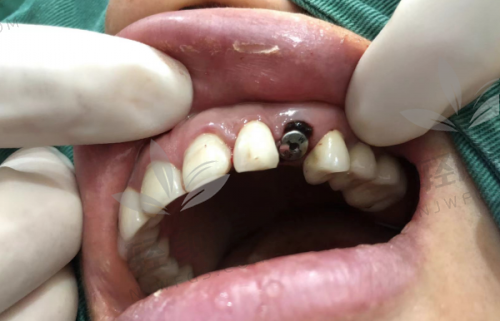

1. 表面技术领跑:比如雅定用的是“第五代活性亲水表面”,能提速骨整合;MIS也有自己研发的喷砂酸蚀SLA工艺,表面像月球那样微孔满满,非常利于骨细胞依附生长;这优质结构可不是随便喷点化学剂就搞定的,都是高真空控制下做的精细工艺。

2. 材料不将就:90%的以色列种植体都采用五级钛,这种材料硬度高、耐腐蚀、抗断裂,是战斗机起落架用的。你种进去它能挺20年,不吹。

3. 设计特别实用:像雅定有超窄2.74mm植体,适合骨量少、牙缝窄的特殊口型;科特斯主打“多种骨质都能用”,对中老年人超级友好。这么一看,真的是细节怪。